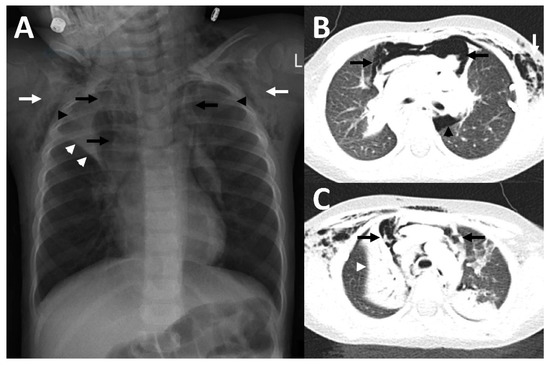

Figure 3.

Imaging findings in patient 3. In the initial chest X-ray, pneumopericardium was suspected (A). Therefore, a CT was performed (B,C) which showed a pneumomediastinum (black arrows), accompanied by a large subcutaneous emphysema (white arrow) and epidural pneumatosis (black arrowhead), but no pneumopericardium. A chest X-ray (D) which was acquired at discharge showed substantial improvement of the previously mentioned findings.